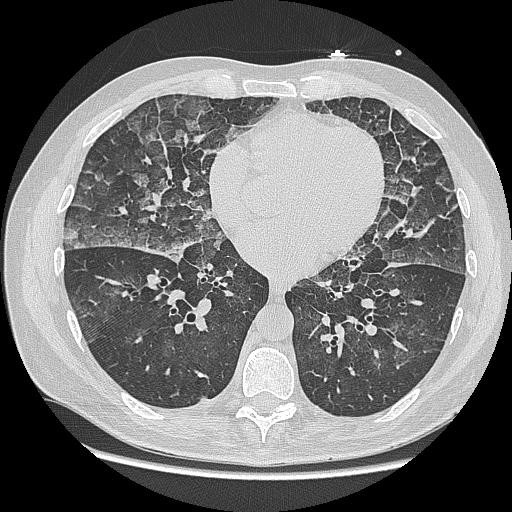

L'œdème pulmonaire d’immersion est un accident qui survient au cours d’activités immergées et qui peut engager le pronostic vital. Le risque de survenue et la gravité augmentent avec l’âge et l’existence de facteurs de risque cardio-vasculaires. Cependant, cet accident concerne aussi les plongeurs militaires, jeunes, sportifs et indemnes de toute pathologie cardio-vasculaire.